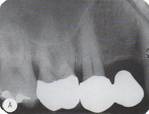

vertical bone loss

Front

Back